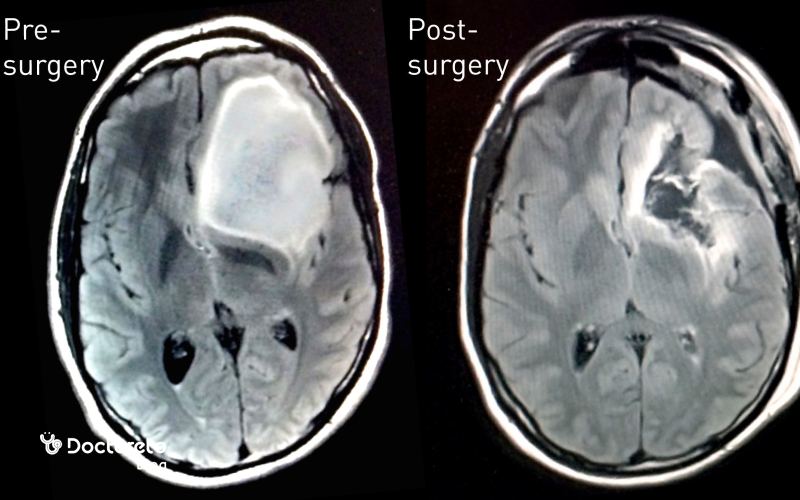

عکس تومور مغزی قبل و بعد از جراحی

عکس‌های قبل از جراحی برای تعیین اندازه و محل دقیق تومور و برنامه‌ریزی مسیر جراحی ضروری هستند. این تصاویر به جراح کمک می‌کنند تا حداقل آسیب به بافت سالم مغز را داشته باشند. بعد از جراحی، تصاویر MRI یا CT برای بررسی میزان برداشته شدن تومور و شناسایی هرگونه تومور باقی‌مانده استفاده می‌شوند. همچنین برای پیگیری روند بهبودی و پیشگیری از عود بیماری، این عکس‌ها به صورت دوره‌ای گرفته می‌شوند.

عکس تومور مغزی بدخیم ابزار مرکزی برای تشخیص، سنجش شدت درگیری و برنامه‌ریزی درمان است. در مراحل اولیه، تصاویر معمولاً توده‌ای کوچک با تفاوت تراکم کم نسبت به بافت طبیعی را نشان می‌دهند و علائم می‌تواند خفیف باشد؛ در مراحل پیشرفته، توده بزرگ‌تر و نامنظم است و فشار بر ساختارهای اطراف و تورم دیده می‌شود. ام‌آر‌آی و سی‌تی‌اسکن امکان تعیین محل، اندازه و گسترش را فراهم می‌کنند و با مقایسهٔ دوره‌ای می‌توان اثر درمان و احتمال عود را ارزیابی کرد. تصاویر پیش و پس از جراحی نیز میزان برداشت تومور و نیاز به اقدامات بعدی را روشن می‌سازند. بدین‌ترتیب، تصویربرداری منظم به تصمیم‌گیری دقیق‌تر کمک می‌کند.